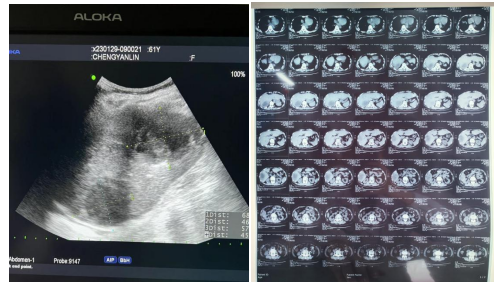

患者超声及CT检查影像

61岁的陈婆婆家住新洲,因右上腹持续性疼痛发热10天,伴有畏寒、高热,在当地医院行补液抗炎治疗,效果不佳,于1月29日到湖北省第三人民医院(省中山医院)阳逻院区就诊。经完善相关检查,超声检查提示:肝内多发无回声区(考虑肝脓肿)。得知检查结果后,陈婆婆及家属说出自己的顾虑:病痛难受、年龄大、术后伤口愈合迟缓、费用受限、家属不方便照顾等,经过普外科、超声影像科、麻醉科多学科会诊,在两院区一体化管理、学科深度融合的背景下,硚口本部超声影像科主任刘琨秉承着对专业的精益求精和不断创新精神和对病人减少创伤、减轻痛苦的原则,为陈婆婆制定了超声引导下肝脓肿穿刺引流方案。

但是陈婆婆非常担心自己年纪大,手术效果不好,始终无法下定决心,最终在医务人员的反复劝说下,陈婆婆最终同意手术。2月10日,刘琨提前到达手术间,仔细询问术前准备情况,并耐心与患者沟通,告知手术流程,缓解其紧张焦虑情绪。术中,刘琨通过超声准确定位病灶,并通过彩色多普勒辨别避让重要血管和胆管,为患者设计安全的进针路径。手术团队成员密切配合为患者实施局部浸润性麻醉,在超声动态观察和实时引导下,18GPTC引导针经正常肝组织3cm精准直达脓腔中央,抽出脓液后,注入适量的抗生素和生理盐水低压冲洗脓肿,迅速改善症状。